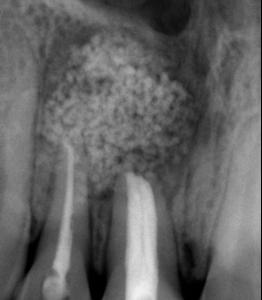

Figura 1. Fotografías intraorales y lateral de cráneo. A. Vista lateral (VL) derecha en oclusión. B. Vista frontal (VF) en oclusión. C. VL izquierda en oclusión. D. Radiografía lateral de cráneo.

Figura 2. Fotografías oclusales y ortopantomografía. A. Vista de la arcada superior. B. Vista de la arcada inferior. C. Ortopantomografía.

Reporte de caso clínico

Paciente masculino de 10 años, se presenta a la consulta en la clínica Gnathos, la mamá reporta desagrado en la estética dental y facial del paciente. En la exploración clínica se observa mordida profunda, amplio número de piezas dentales con caries, fracturas dentales, mala higiene y encías inflamadas. presenta clase II división 2, se le indicaron estudios complementarios para diagnóstico asertivo, modelos de estudio,

Tratamiento de mordida profunda

radiografía panorámica y lateral de cráneo, fotografía intraoral y extraoral, historia clínica y consentimiento informado.